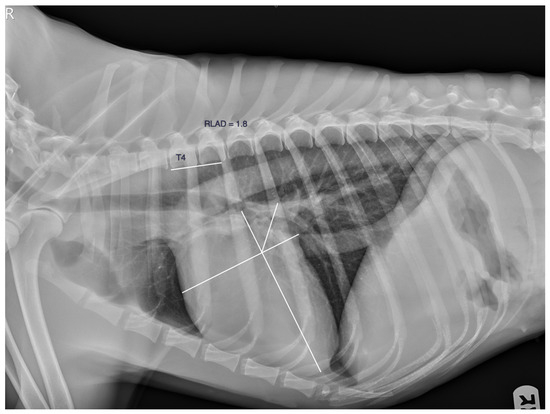

- Sánchez Salguero, X.; Prandi, D.; Llabrés-Díaz, F.; Manzanilla, E.G.; Bussadori, C. A radiographic measurement of left atrial size in dogs. Ir. Vet. J. 2018, 71, 25. [Google Scholar] [CrossRef] [PubMed]